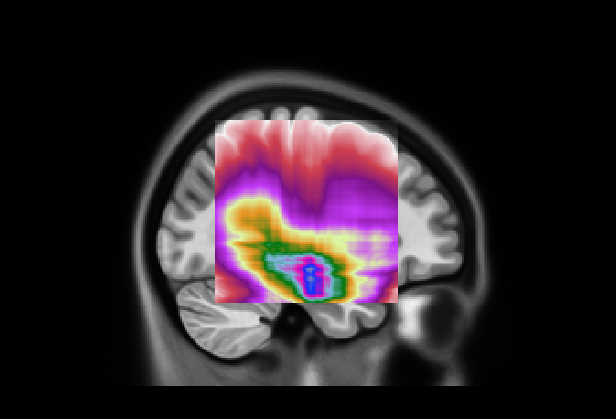

Figure 9: (Left) Visualization of mean 3D GradCAM++ map of entire dataset overlapped to MNI152 template with our model; (Right) Visualization of mean 3D GradCAM++ map of entire dataset overlapped to MNI152 template with Attention Transformer;

We also examined the interpretability of the Attention Transformer model proposed in (Altay et al., 2021). For comparison, we created 2D saliency maps using the GradCAM++ algorithm (Chattopadhay et al., 2018) across all three views and all five test sets from the different folds. These maps were combined to create a unified average 3D saliency map as outlined in Section 7. This method was also applied to generate equivalent results from the saliency maps produced using our diagnostic model. As shown in Fig. 8, the 2D maps produced by our method are generally sparser compared to those from the Attention Transformer. The method introduced in (Altay et al., 2021) employs a cross-attention mechanism via a Multi-Head. Therefore, it is plausible that the Multi-Head allows to generate 2D maps that align more meaningfully within the 3D context. This finding suggests that our approach may consider less contextual information from adjacent slices unless it is particularly relevant. In contrast, the cross-attention in the Attention Transformer might enable a more cohesive representation of the entire 3D space by considering both the local features within slices and their contextual interactions. This behavior is further clarified by creating 3D maps and overlaying them on the MNI152 template, similar to the attentional maps. As illustrated in Fig. 9 on the left, the 3D maps created using our model cover a broader and less concentrated area compared to those produced by the Attention Transformer, which are shown on the right. However, similar to the 3D attentional maps, both models predominantly focus on an area surrounding the hippocampus. As detailed in Table 9, both models identify key areas, such as the hippocampus and the amygdala, as significant. However, the emphasis on other regions varies markedly between the two. In the attention transformer model, there is a noticeable focus on the inferior lateral ventricles and the parahippocampal region, areas less emphasized by our model in this case. This result indicates that the Attention Transformer using cross-attention in combination with GradCAM can produce results similar to those obtained by our method with a 3D attentional map. As seen in Tables 8(a) and 9(b), the first four areas on which our model focused with our approach are the same as those focused on by Attention Transformer with GradCAM. In contrast, our model with GradCAM shows broader involvement with regions such as the superior and middle temporal areas, which are not as prominent in the other cases.